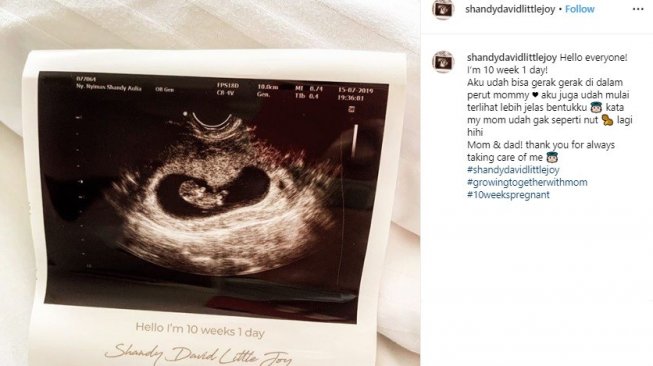

Sedang hamil, ini 10 foto USG yang kerap dipamerkan Shandy Aulia

Sedang hamil, ini 10 foto USG yang kerap dipamerkan Shandy Aulia

Sedang hamil, ini 10 foto USG yang kerap dipamerkan Shandy Aulia

Sedang hamil, ini 10 foto USG yang kerap dipamerkan Shandy Aulia